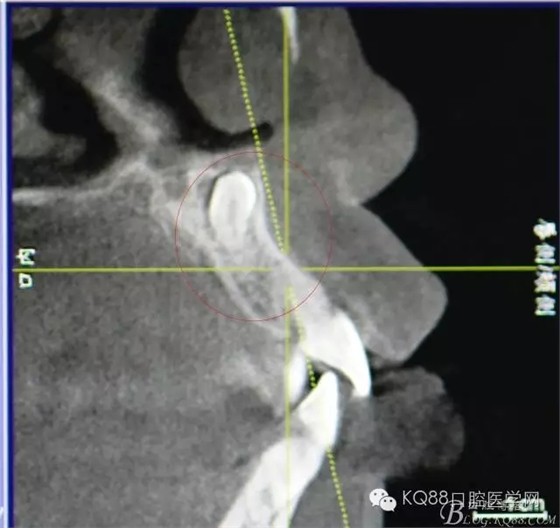

圖2.CBCT矢狀面影像檢查:多生牙牙冠上方與鼻底僅有黏膜相隔

圖3.CBCT三個(gè)方向剖面圖影像:多生牙牙根阻擋11內(nèi)收、牙冠接近鼻底